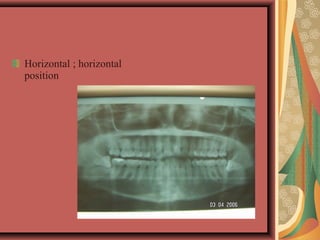

Horizontal - long axis of the third molar perpendicular

to the second molar

Horizontal ; horizontal

position